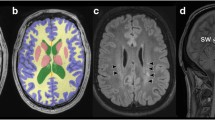

Two board-certified radiologists with 6 years experience evaluated FLAIR and T1-weighted images blinded to birth status. Supratentorial hyperintense lesions on FLAIR-weighted imaging were counted separately depending on their localization (periventricular, deep white matter, subcortical). Subcortical localization was defined as a distance <3 mm from the cerebral cortex, periventricular localization was defined by direct contact with the ventricular surface. Examples of periventricular, deep white matter and subcortical FLAIR hyperintense lesions are shown in Fig. 1. Lateral ventricle volume (LVV) was rated subjectively based on the radiologist’s impression in a yes or no fashion. Additionally, the Evans’ index (EI) and FOHR were measured as described previously [30]: the EI is defined as the ratio between the largest axial diameter of the frontal lateral ventricle horns and the biparietal diameter [31] and FOHR is defined as the sum of largest axial frontal horn and occipital horn diameter divided by double the biparietal diameter [30]. Due to the well-established excellent intrarater and interrater reliability [32], EI and FOHR were only measured by reader 1. Incidental findings were noted as free text.

Fluid-attenuated inversion recovery (FLAIR) lesion localization. Examples of FLAIR hyperintense white matter lesions in periventricular (a), deep white matter (b) or subcortical (c) localization. Periventricular FLAIR lesions abut the ventricular surface, subcortical FLAIR lesions lie within 3 mm of the cortical ribbon, without direct contact. Representative lesions are marked with a red arrow

The ROC analysis revealed AUC of 0.928 (p < 0.001) and 0.880 (p < 0.001) for FOHR and EI, respectively. Youden’s J was calculated to identify the optimal cut-off for identifying abnormal LVV for both measures, leading to a value of 0.37 for FOHR and 0.27 for EI. These values were associated with sensitivities of 96.3% and 77.8% and specificities of 73.8% and 81.9% for FOHR and EI, respectively. The ROC curve is shown in Fig. 2.

Prematurity is Associated with Deep White Matter Lesions on FLAIR Imaging in Adulthood

The FLAIR lesions were counted by two board-certified radiologists independently. Intraclass correlation coefficient (ICC) showed good to excellent agreement [34] (periventricular FLAIR lesions ICC = 0.945, 95% CI = 0.928–0.958; deep white matter FLAIR lesions ICC = 0.878, 95% CI =0.840–0.908; subcortical flair lesions ICC = 0.845, 95% CI = 0.796–0.882). All statistical analyses performed led to the same significant or insignificant results for reader 1 and 2. In the following, detailed numbers of the more experienced reader 1 are shown for reasons of simplicity and readability. A total of 115 individuals (55.8%) were positive for at least one FLAIR hyperintense WML in any location (VP/VLBW: 60/FT: 55; p = 0.259), 31 individuals (15.0%) were positive for periventricular FLAIR lesions (VP/VLBW: 24/FT: 7; p = 0.001), 49 individuals (23.8%) were positive for deep white matter FLAIR lesions (VP/VLBW: 33/FT: 16; p = 0.003) and 84 individuals (40.8%) were positive for subcortical FLAIR lesions (VP/VLBW: 35/FT: 49; p = 0.103). Detailed information on the distribution of periventricular, deep white matter, and subcortical FLAIR lesions can be found in Table 2, examples are shown in Fig. 1.

Ventriculomegaly is a mostly idiopathic and unspecific neuroradiological imaging finding potentially indicating either hydrocephalus or parenchymal atrophy. These two etiologies can be reliably distinguished by midsagittal morphological changes such as stretching and displacement of the corpus callosum, widening of the third ventricular recessus, and decreased mamillopontine distance [36]. We confirmed the expected low rate of ventricular enlargement in control individuals born at full-term; however, one out of four prematurely born adults exhibited enlargement of the LV, making this a common incidental finding after prematurity. In line with previous studies from prematurely born infants and adolescents, we demonstrated higher mean LVV in prematurely born adults [37, 38]. Larger LVV was significantly predicted by lower GA and incidence of PVH in the neonatal period, suggesting a parenchymal white matter deficit caused by either white matter dysmaturation and/or direct damage by ICH. Comparing three approaches regarding the evaluation of LV size in young adults, we have identified the FOHR as the most accurate measure being feasible in clinical routine [30]. This superior accuracy of the FOHR is most likely caused by occipital horn dilatation in prematurely born adults which was described previously [39].